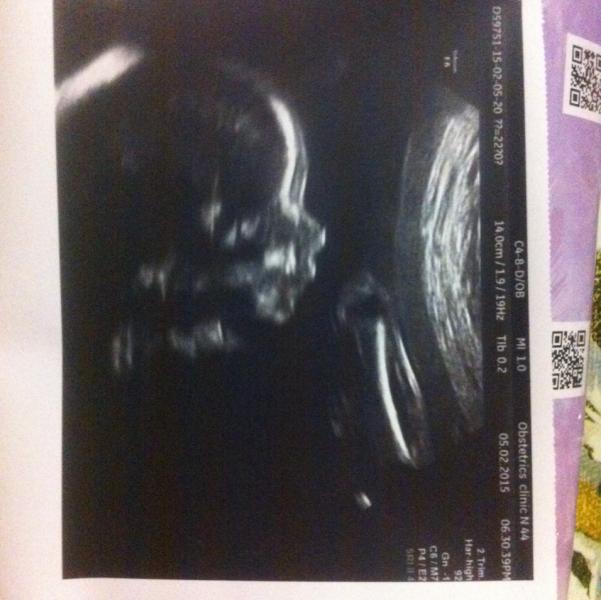

Самое главное - мы теперь точно знаем пол! Мы ждем второго мальчика!!!

Выдали фото, так что сомнений просто не осталось :)

@9114440, фото которое в комментариях - сверху попа, от нее две ножки. Вид снизу, малыш как бы сидит на датчике. Между ног - мошонка и писюн